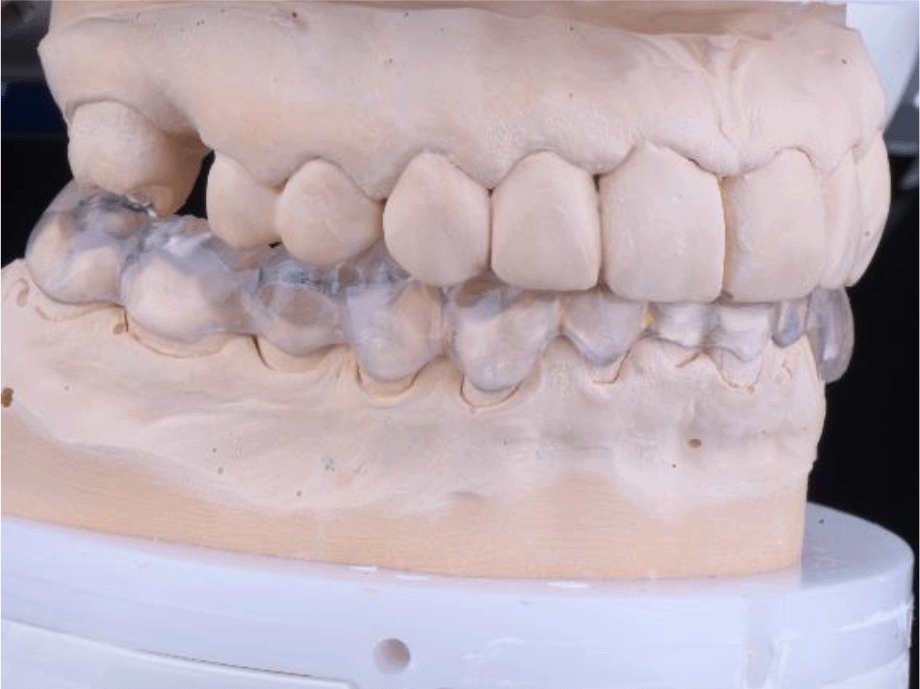

The patient reported a lack of symptoms of TMJ after 3 months, establishing the therapeutic effect of the splint. We then proceeded to the final prosthesis. All constructions were made of ceramics based on zirconium dioxide, with added yttrium and hafnium oxides. The distal defects of the lower jaw were solved with bridge constructions, and single crowns were placed on the frontal teeth (Figures 19 and 20).

26dd931c-41d3-478d-bec1-8cb211d0a4b8_figure19.gif

Figure 19. Zirconia prosthesis on the model.

26dd931c-41d3-478d-bec1-8cb211d0a4b8_figure20.gif

Figure 20. Zirconia prosthesis in the patient’s mouth (try-in procedure).

All of the final constructions were made from Ceramill Zolid FX MultiLayer B2 and Glase (AmannGirrbach). For the upper jaw, single zirconia crowns of the canines and block crowns of 11, 12 and 21, 22, respectively, were made, for the distal defects - bridge restorations of zirconia ceramics. The distal structures of both jaws were cemented first to ensure stable occlusion. Then the crowns were fixed almost at the same time in the frontal section (Figures 21 and 22).